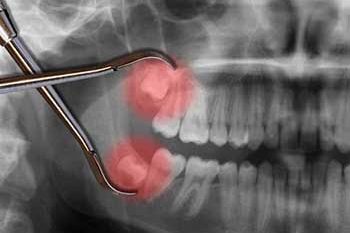

Why do wisdom teeth cause pain? Wisdom teeth do not always come out all the way (fully erupt), when there is not enough space in the mouth for them. They partially erupt, which means the gum does not fully seal the tooth, sometimes causing a gum flap. Due to the location, it is often difficult…